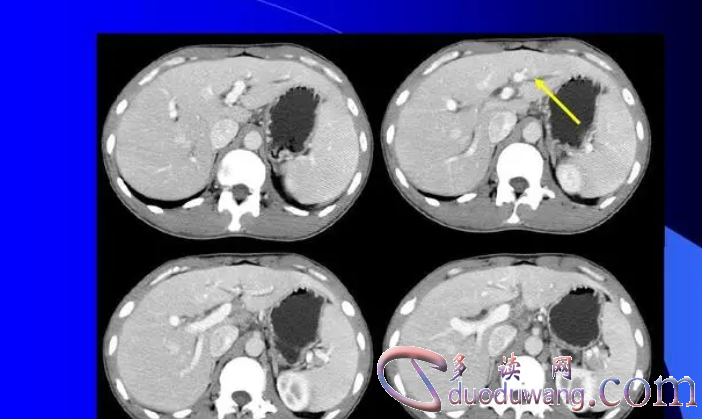

针对肝外胆管扩张,通常需要进行详细的检查和评估,包括血液检测、超声波或CT扫描,以确定胆管扩张的原因和程度。治疗方法包括调整饮食、药物治疗和必要时手术干预。同时,患者在日常生活中也需要注意饮食习惯和生活方式,避免诱发肝胆疾病的因素,保持身体健康。